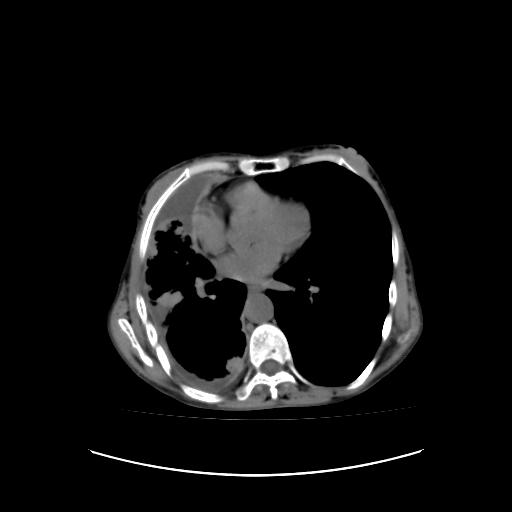

标题: CT16930:女 59 胸痛6个月 胸水脱落细胞学见瘤细胞 [打印本页]

可见多发肺内病灶,且胸膜病灶较多有圆球状而非丘状,多考虑胸膜转移瘤伴胸腔积液,右侧胸廓缩小固定,且部分病灶呈丘状,尚不除外恶性胸膜间皮瘤伴肺内转移

右侧胸膜增厚,局部呈结节状增厚,右侧胸腔少量积液。双肺未见确切肿块影。纵隔未见淋巴结肿大。气管、支气管通畅。考虑右侧胸膜间皮瘤(恶性?)可能性大。不除外癌性胸膜炎。

恶性胸膜间皮瘤伴肺内转移可能性大;或胸膜、肺内均为转移瘤,左肺下叶亦见多发小结节影。

右侧胸廓塌陷,右侧胸膜广泛增厚并见多发胸膜结节,右侧少量胸腔积液并包裹。

右侧广泛胸膜增厚,局部呈结节状增厚,右侧胸腔少量积液。双肺未见确切肿块影。纵隔未见淋巴结肿大。气管、支气管通畅。考虑右侧胸膜间皮瘤(恶性?)可能性大。支持!

右侧胸膜转移瘤,原发灶可能就在在右肺,另外建议检查右侧乳腺.

右胸腔结节均考虑来自胸膜(部分来源于叶裂),考虑胸膜间皮瘤或转移瘤.